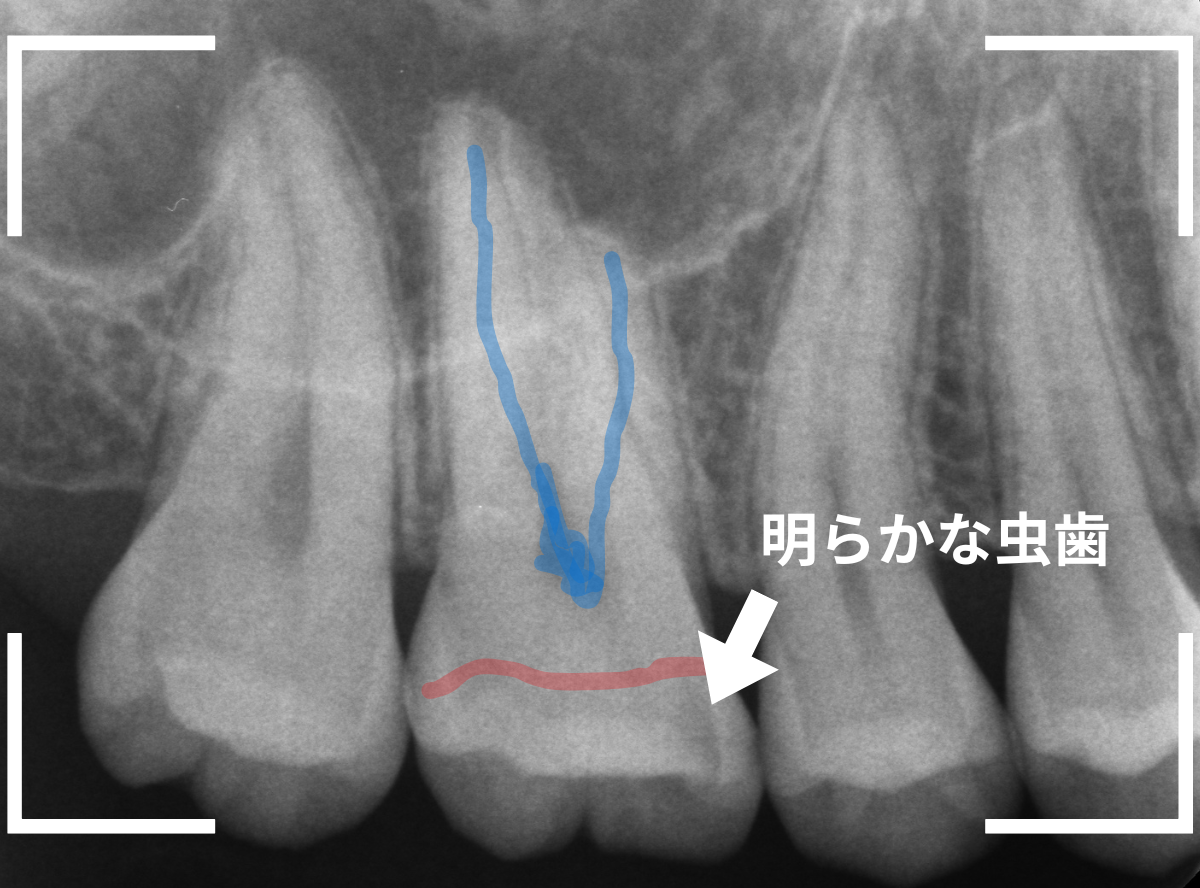

レントゲン写真で確認します。

赤いラインが虫歯と思われる部分、青いラインが歯の神経です。

先ほどの〇部分は明らかな虫歯になっているのがわかります。

この辺りはレジンがつめてありますが、その下もうっすらと虫歯になっていそうです。